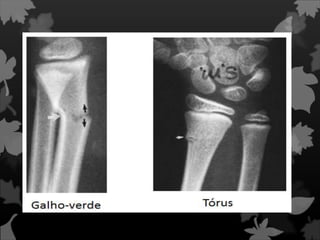

Fratura de Galhoverde Fratura típica que ocorre na criança, onde há extrema elasticidade do osso. Um dos córtices quebra e o outro fica “amassado”.

Fratura de Toro

Fratura Incompleta Nesse tipode fratura o osso não é fraturado em duas partes, mais comum em crianças. Também é conhecida como fratura em fissura.